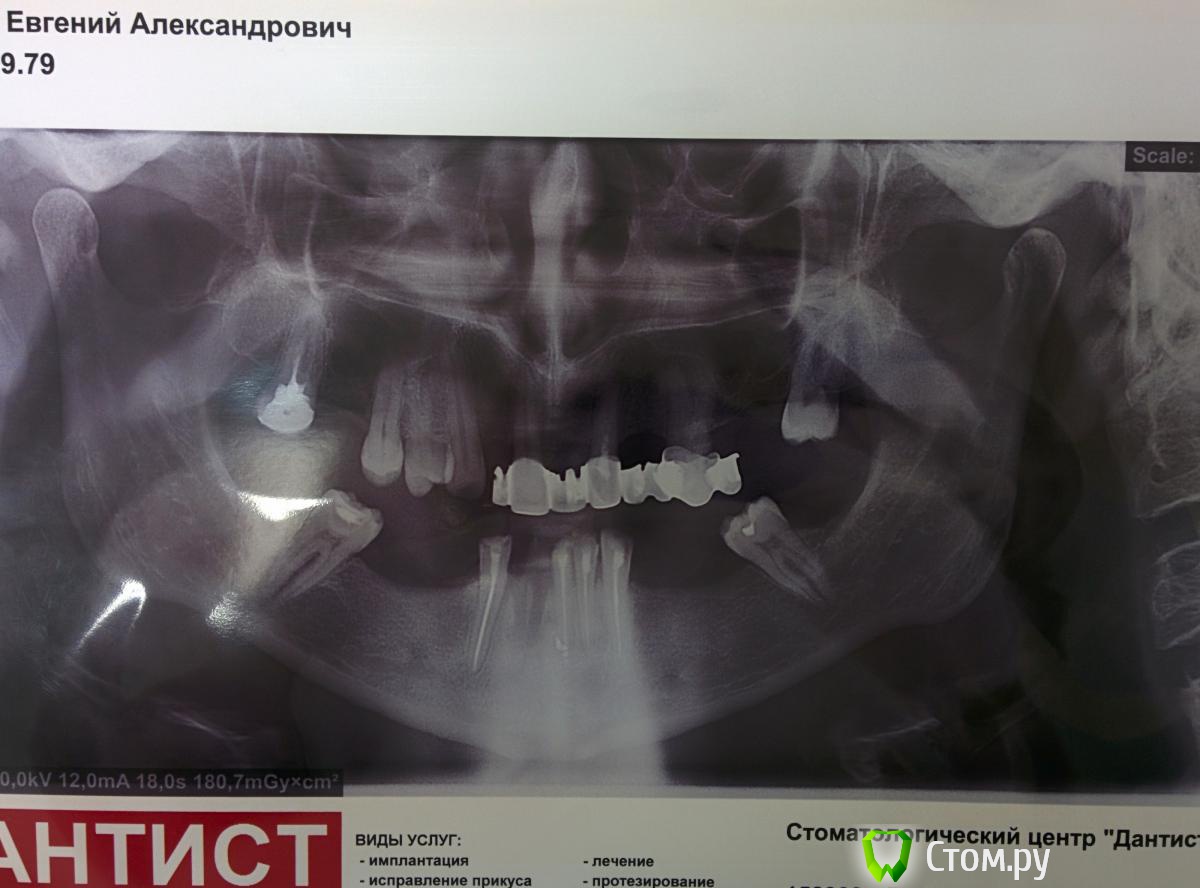

chervoncevdaniil Опубликовано 11 августа, 2014 Автор Поделиться Опубликовано 11 августа, 2014 Доктора,новый пациент,проблемный для меня,фото конечно,плохие,но пока нет нормального оборудования для фотографии.Завтра приложу фото моделей.Посоветуйте,пожалуйста,что можно придумать.Бюджет ограничен суммой в 80000,при цене мк-5000,цл-3000,имплант 20000.ТО есть имплантация и ортодонтия скорее всего отпадают сразу. 1 Ссылка на комментарий

Rash163 Опубликовано 11 августа, 2014 Поделиться Опубликовано 11 августа, 2014 Доктора,новый пациент,проблемный для меня,фото конечно,плохие,но пока нет нормального оборудования для фотографии.Завтра приложу фото моделей.Посоветуйте,пожалуйста,что можно придумать.Бюджет ограничен суммой в 80000,при цене мк-5000,цл-3000,имплант 20000.ТО есть имплантация и ортодонтия скорее всего отпадают сразу.Да уж, не повезло пациенту, он свои зубы должен был береч и береч(( сам он что хочет. Есть мнение здесь далеко не 80 Ссылка на комментарий

chervoncevdaniil Опубликовано 11 августа, 2014 Автор Поделиться Опубликовано 11 августа, 2014 Да уж, не повезло пациенту, он свои зубы должен был береч и береч(( сам он что хочет. Есть мнение здесь далеко не 80Ну прям уж Голливуд ему не надо,но более менее в приличный вид привести все хочет.Я просто не понимаю что с таким прикусом делать ичто можно с ним сделать только ортопедически Ссылка на комментарий

doktor vv Опубликовано 11 августа, 2014 Поделиться Опубликовано 11 августа, 2014 Даниил,портретную съемку делаете?(профиль,анфас)Здесь 3ий класс-было бы неплохо сделать ТРГВ идеале в данном кейсе без ортохирургии ничего не сделатьПри бюджете в 80 рублей работать придется в существующей окклюзииЖдем моделей Ссылка на комментарий

alekszander Опубликовано 13 августа, 2014 Поделиться Опубликовано 13 августа, 2014 Я вначале не понял прикус, потом всмотрелся... пипец. Уж насколько я берусь за все, на что хватает духу (не подумайте не за все подряд, только ради бабосиков). Здесь полная(ый) жо(ахтунг)! Конечно видеть нужно модели. Но скорее всего только через хирургическую ортодонтию, что то получится путевого. Ну и про 80 тут даже речи не идет. Объясните что ему показано, зачем это нужно и расскажите что сроки до окончания будут очень, ну так сказать длительные... А так ждем фото с моделями со всех ракурсов. И прежде чем взяться я бы долго планировал, наверное бы несколько раз в перерывах по 2-3 дня (чтоб мозг остывал) с книгами на руках. Но я такой, никуда не спешу особо и другим не советую. Ссылка на комментарий

doktor vv Опубликовано 13 августа, 2014 Поделиться Опубликовано 13 августа, 2014 Так я взял перерыв до пятницы, модели выложу, может хоть кто нибудь из исходных данных скажет что тут можно придуматьДепульпированные зубы те что не удалять-коронкиФронт верхней челюсти -коронки2 съемникаИ все это в привычной окклюзииХотя и так в 80 рублей не уложитьсяКак вариант-фронт коронки и 2 сьемникаПо моделям вряд ли что изменится разве что съемники сделать не удастсяНо это все очень компромиссные вариантыЯ бы отказался,все же без ортохирургии получится не оченьА вот гигиена,лечение кариеса и коронки на сильно разрушенные зубы можно попробовать Ссылка на комментарий

doktor vv Опубликовано 13 августа, 2014 Поделиться Опубликовано 13 августа, 2014 На верхней челюсти остается только фронт-коронки и съемный.На нижней съемник бы не стал делать скорее мосты( Ссылка на комментарий

alekszander Опубликовано 14 августа, 2014 Поделиться Опубликовано 14 августа, 2014 На верхней челюсти остается только фронт-коронки и съемный.На нижней съемник бы не стал делать скорее мосты(и как вы будете протезировать подскажите поподробнее? я смутно представляю коронки на фронт и съемники. Первое это для этого придется поднять прикус, и как в такой ситуации ответит сустав? Ссылка на комментарий

alekszander Опубликовано 14 августа, 2014 Поделиться Опубликовано 14 августа, 2014 IMG_20140813_205924.jpgIMG_20140813_205939.jpgIMG_20140813_205949.jpgОбещанные фото моделей.Доктора,пациент на пятницу назначен,возможные варианты посоветуйте,пожалуйста.У меня есть собственные мысли на этот счет,хотелось бы от вас послушатьДля меня лично жесть и если честно, то я даже не представляю что тут подсказать без хирургической ортодонтии. Куда не копни, везде есть нюансы которые не позволяют адекватно протезировать в данном случае. А подскажите, что пациента то беспокоит, чего хочет он?PS я бы отправил на ортодонтию и даже бы не стал ничего без нее делать. можно потом хапнуть сильно. Ссылка на комментарий